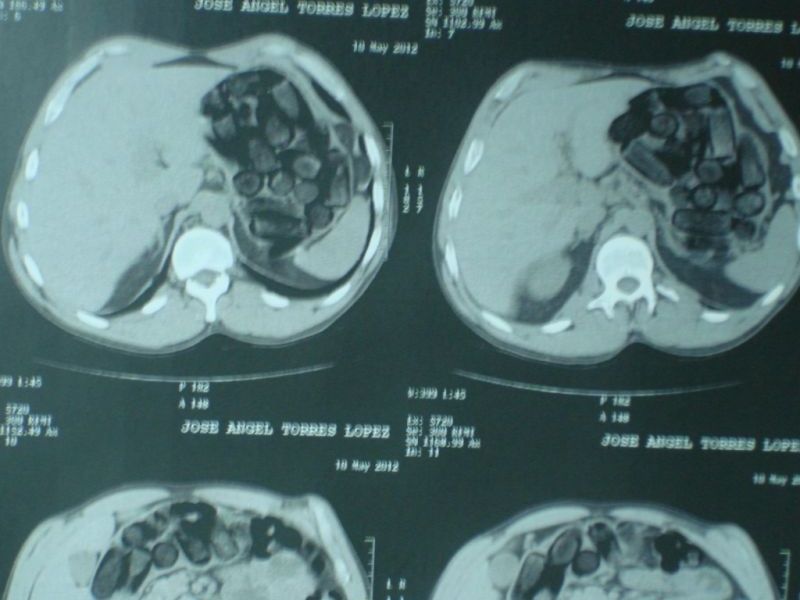

No Hospital Municipal de Foz do Iguaçu, um exame de ressonância magnética confirmou a presença da droga. Por causa do risco de morte caso alguma das cápsulas se rompa antes de ser expelida, o acusado ficará em observação e assim que deixar o hospital será levado para a carceragem da delegacia da PF. A pena nestes casos varia de 5 a 15 anos de prisão, mais multa.